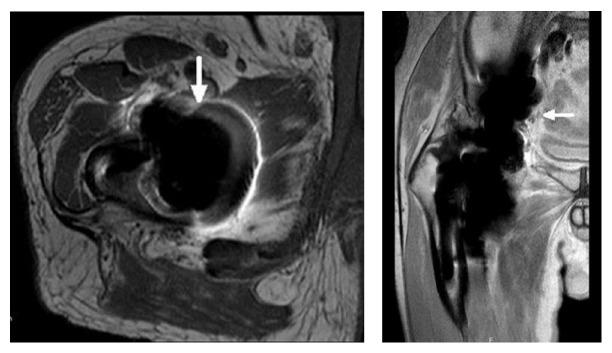

This case illustrates the potential for systemic cobalt toxicity in non-metal-on-metal bearings and its potentially devastating consequences. We present a 71-year-old male with grinding sensations in his right hip following ceramic-on-ceramic total hip arthroplasty (THA). After diagnosing a fractured ceramic liner, the hip prosthesis was revised into a metal-on-polyethylene bearing. At one year postoperatively, X-rays and MARS-MRI showed a fixed reversed hybrid THA, with periarticular densities, flattening of the femoral head component, and a pattern of periarticular metal wear debris and pseudotumor formation. Before revision could take place, the patient was admitted with the clinical picture of systemic cobalt toxicity, supported by excessively high serum cobalt and chromium levels, and ultimately died. At autopsy dilated cardiomyopathy as cause of death was hypothesized. A third body wear reaction between ceramic remnants and the metal femoral head very likely led to excessive metal wear, which contributed systemic cobalt toxicity leading to neurotoxicity and heart failure. This case emphasizes that fractured ceramic-on-ceramic bearings should be revised to ceramic-on-ceramic or ceramic-on-polyethylene bearings, but not to metal-on-polyethylene bearings. We aim to increase awareness among orthopedic surgeons for clinical clues for systemic cobalt intoxication, even when there is no metal-on-metal bearing surface.

该病例说明了在非金属对金属轴承中发生全身钴中毒的可能性及其潜在的灾难性后果。我们报告一名71岁男性,在接受陶瓷对陶瓷全髋关节置换术(THA)后右髋出现磨削感。在诊断为陶瓷内衬骨折后,将髋关节假体翻修为金属对聚乙烯轴承。术后一年,X线和MARS-MRI显示为固定的反向混合型THA,有关节周围密度、股骨头部件扁平,以及关节周围金属磨损碎片和假肿瘤形成的表现。在进行翻修之前,患者因全身钴中毒的临床表现入院,血清钴和铬水平过高支持了这一诊断,最终患者死亡。尸检推测死亡原因是扩张型心肌病。陶瓷残余物与金属股骨头之间的三体磨损反应很可能导致了过度的金属磨损,这导致了全身钴中毒,进而导致神经毒性和心力衰竭。该病例强调,陶瓷对陶瓷轴承骨折应翻修为陶瓷对陶瓷或陶瓷对聚乙烯轴承,而不应翻修为金属对聚乙烯轴承。我们旨在提高骨科医生对全身钴中毒临床线索的认识,即使不存在金属对金属轴承表面。